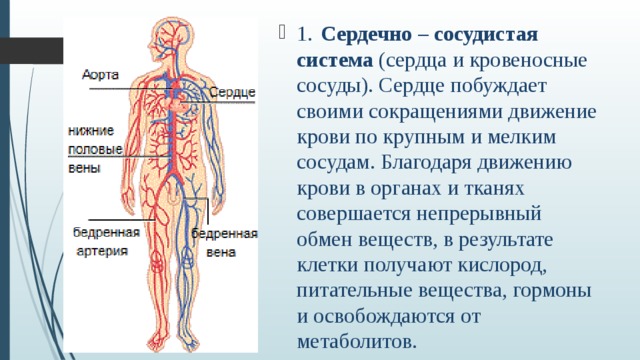

Кровеносная система человека: структура и функции

Раздел: Идеи и советы